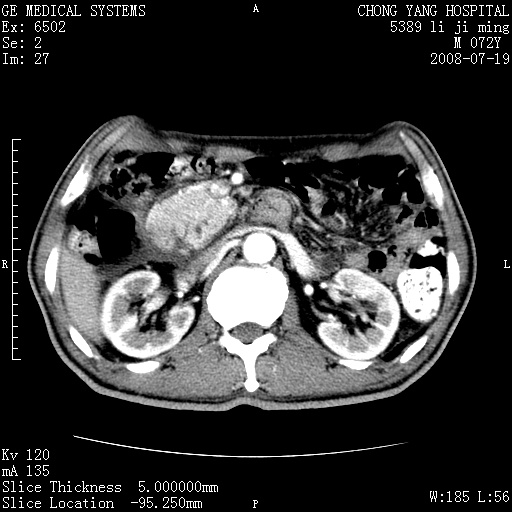

以下是引用zjzjr在2008-7-19 20:57:00的发言:[br]胰头增大,边缘模糊,周围可见渗出影,右侧肾前筋膜增厚.支持胰腺炎.

以下是引用yangyudong333在2008-7-20 6:56:00的发言:[br]胰腺增大尤以胰头明显,边缘模糊,周围可见渗出影,右侧肾前筋膜增厚,肠管於涨.支持胰腺炎

以下是引用不学无术在2008-7-19 23:15:00的发言:[br]胰腺增大尤以胰头明显,边缘模糊,周围可见渗出影,右侧肾前筋膜增厚,肠管於涨.支持胰腺炎